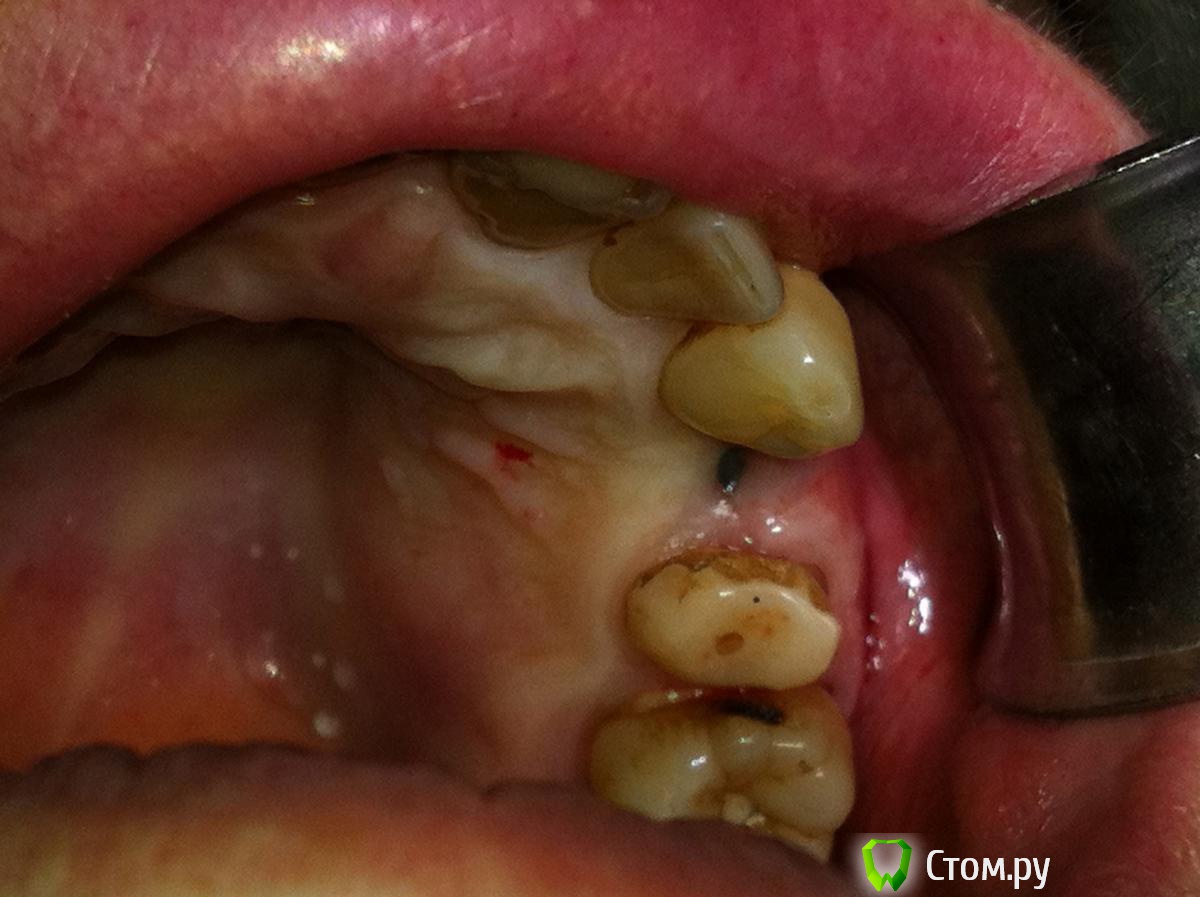

Tabula Rasa Опубликовано 29 сентября, 2014 Поделиться Опубликовано 29 сентября, 2014 (изменено) Пациент Л, 65 летИмплантация в области 2.4. Ожидание 4-4.5 месяца->недостаток мягких тканей и к тому же явный "завал" вестибулярного овала->ротированный лоскут на ножке одновременно фиксируемый формирователем->1 месяц->протезирование.Окончательным результатом не до конца доволен,т.к десна все равно усела и по высоте,и по ширине...думается ошибка в отсутствие временной коронки на импланте была. Изменено 29 сентября, 2014 пользователем IlyaPM Ссылка на комментарий

syrovovec Опубликовано 30 сентября, 2014 Поделиться Опубликовано 30 сентября, 2014 Немного нёбнее нужно было ставить и сст при установке, а на раскрытия добавить если что, По толщине мне нравиться, а по высоте вроде маловато Ссылка на комментарий

Mane Опубликовано 30 сентября, 2014 Поделиться Опубликовано 30 сентября, 2014 Ошибка в методе пластики десны. Здесь был нужен гамборенинг! 4 Ссылка на комментарий